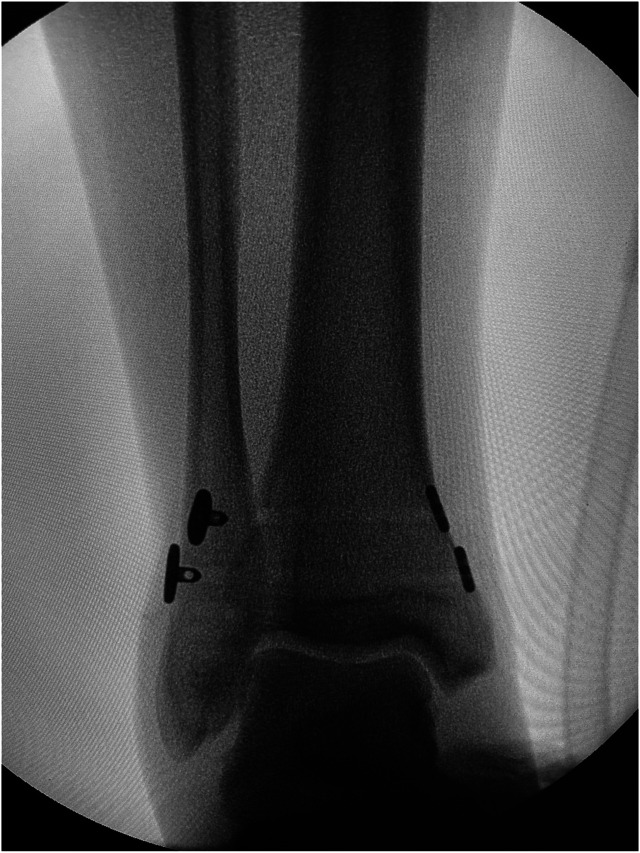

Background: Ankle injuries, often involving the syndesmotic complex, are common and may lead to acute instability. The syndesmosis, comprising several key ligaments, provides critical support for ankle function. This study assesses the efficacy and safety of the suture button system for isolated syndesmotic injuries, a treatment method that is gaining popularity over traditional transsyndesmotic screws.

Methods: A retrospective review was conducted on patients treated surgically with the suture button system for isolated syndesmotic injuries from January 2018 to December 2023. Key outcomes measured included time to full weight-bearing, returning of daily activities, and complications. The study also compared these outcomes with historical data from screw fixation methods.

Results: Thirty-two patients (20 men, 12 women; mean age 41.66 ± 16.57 years [range 16-72 years]) were analyzed over an average follow-up of 9.94 ± 5.49 months (range 3-28 months). Patients achieved full weight-bearing at 1.23 ± 0.31 months postoperatively, resumed daily activities with restrictions at 3 ± 1.09 months, and without restrictions at 6.67 ± 2.55 months. No major complications were reported; minor complications included implant removal due to irritation in two patients (6.25%) and minor wound issues in one patient (3.13%).

Conclusion: The suture button system demonstrated good outcomes in allowing physiological motion, low malreduction rates, and minimizing reoperation needs. The present results indicate a promising safety profile and functional recovery, despite limitations such as small sample size and lack of patient-reported outcome measures.